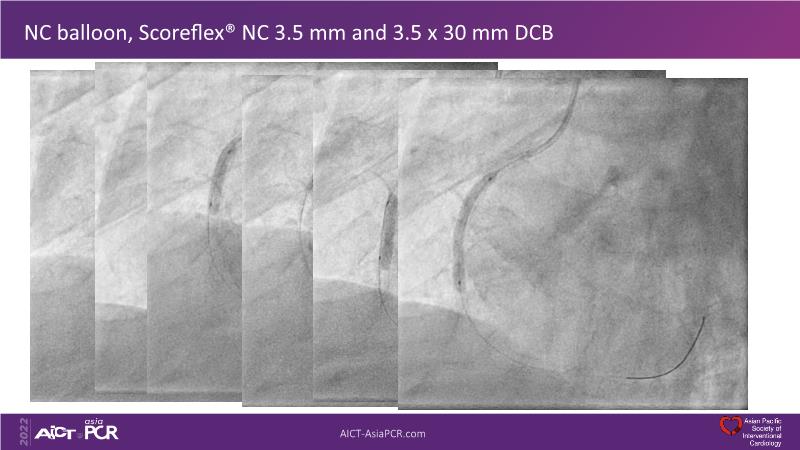

In this session, presenters describe how to use IVUS and physiology in the assessment of left anterior descending and/or left circumflex ostium in distal left main disease. Discover in the second part the general principles and clinically validated strategies for ultralow contrast coronary angiography and zero contrast percutaneous coronary intervention.

- To learn how imaging can help with strategising left main PCI, plaque preparation, device sizing and optimising results